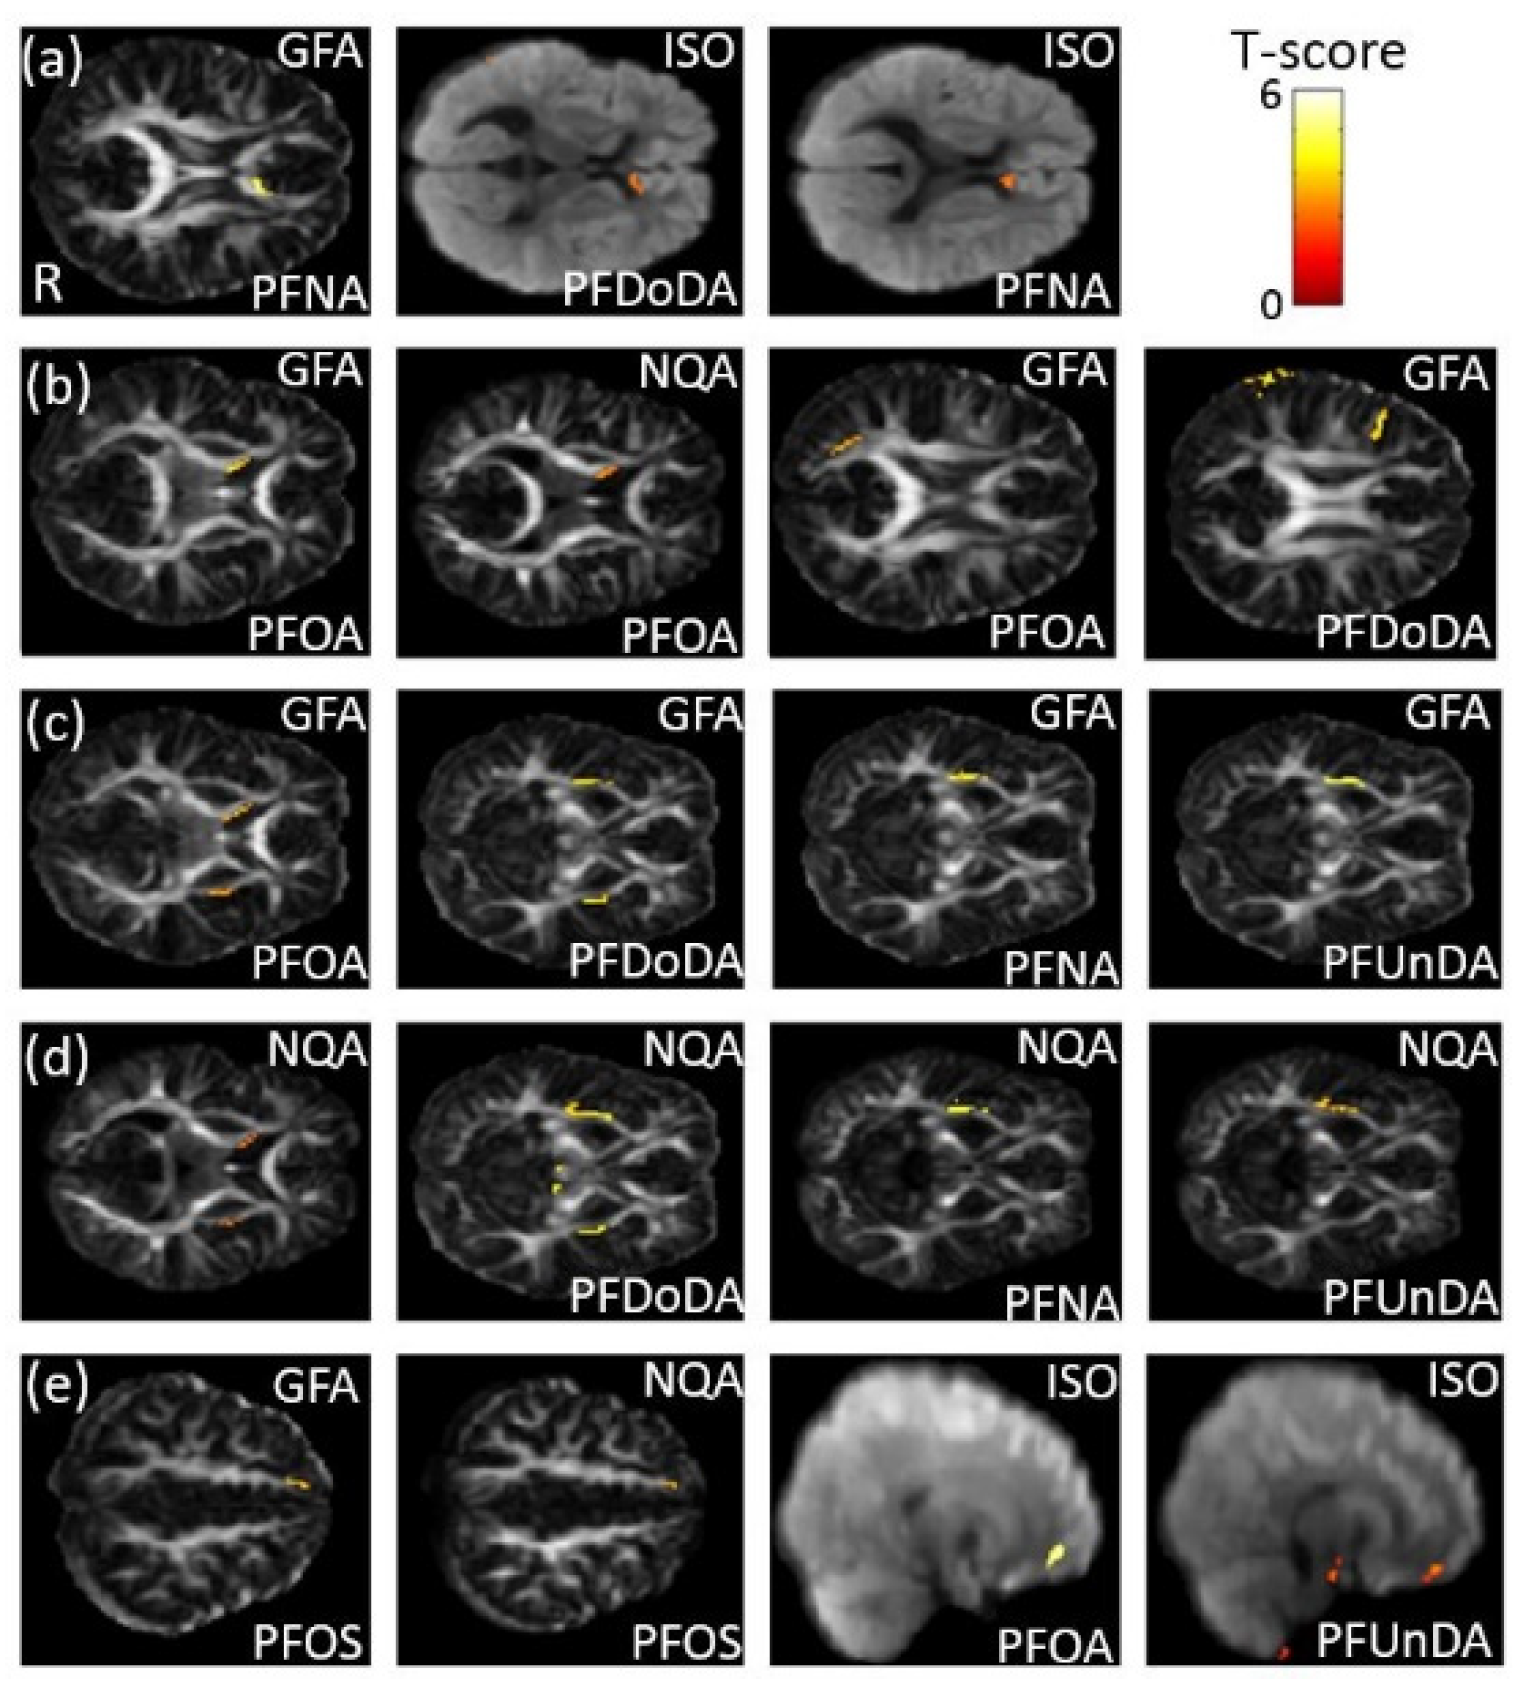

3.6. The Association between PFCs and GQI